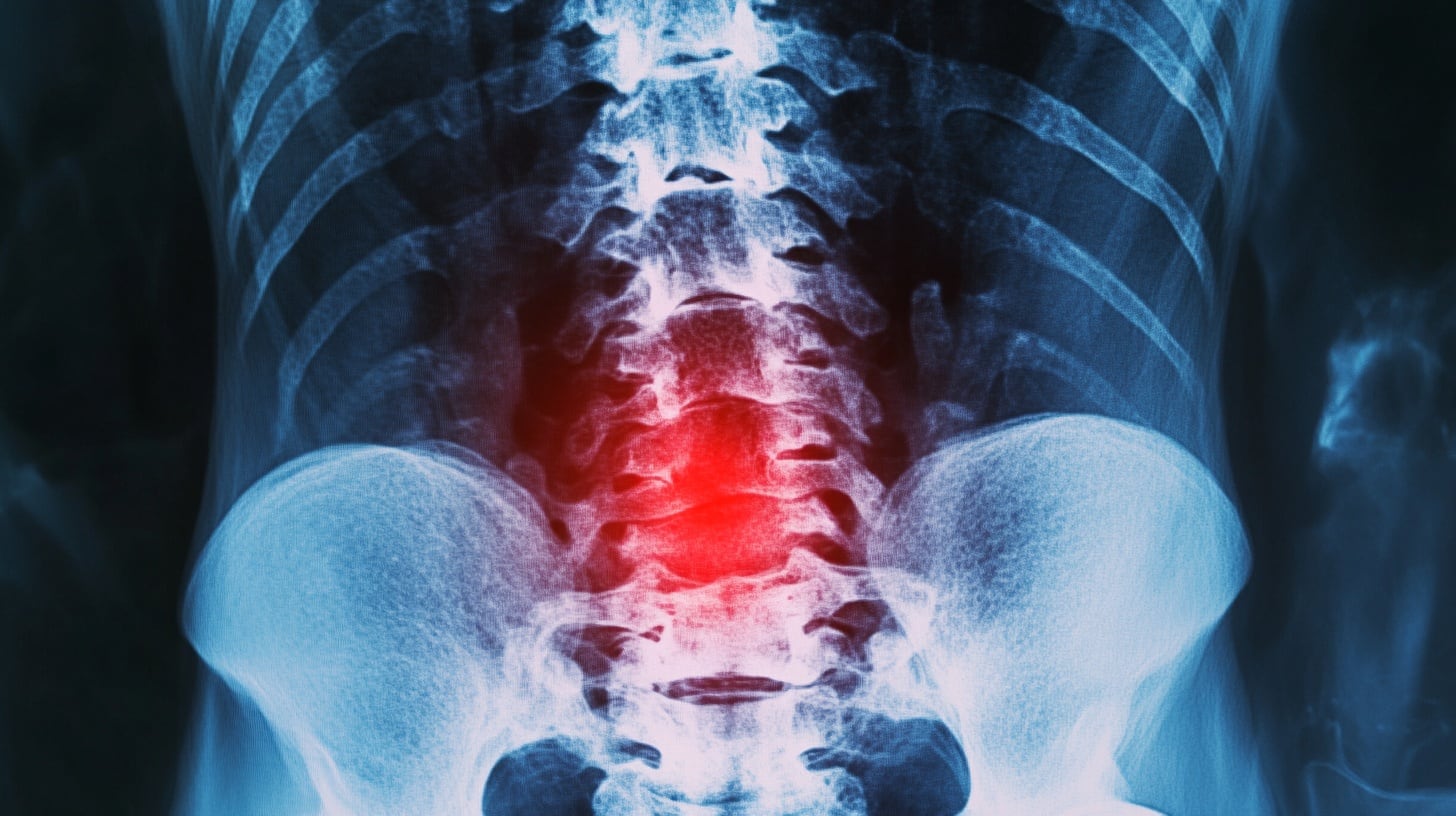

El dolor de espalda en hombres mayores puede anticipar un aumento en el riesgo de problemas de sueño varios años después, según un estudio realizado por la Universidad Estatal de Pensilvania. El seguimiento a más de 1.000 hombres mayores de 65 años en Estados Unidos reveló que quienes reportaron dolor de espalda presentaron entre un 12% y un 25% más riesgo de desarrollar trastornos del sueño seis años después.

El Colegio Estadounidense de Reumatología resalta que el dolor de espalda es una de las causas más frecuentes de consulta médica. Se calcula que hasta el 80% de la población mundial padecerá este problema en algún momento. Las causas más comunes incluyen la distensión muscular por esfuerzos o posturas incorrectas, el envejecimiento natural de los discos y las articulaciones de la columna, así como las hernias de disco y la estenosis espinal. El dolor lumbar, término que describe las molestias en la zona baja de la espalda, puede volverse crónico y suele agravarse con la edad, provocando rigidez o irradiación a las extremidades.

De acuerdo con el Colegio, el diagnóstico del dolor de espalda debe iniciarse con una valoración clínica y examen físico, reservando los estudios de imagen para casos específicos. La mayoría de los episodios no requieren cirugía y responden bien a la fisioterapia, la actividad física adaptada y analgésicos de venta libre. Se recomienda mantenerse activo, evitar el reposo prolongado y realizar ejercicios de estiramiento y fortalecimiento muscular. El sobrepeso y las malas posturas son factores de riesgo adicionales, mientras que dejar de fumar y mantener una alimentación equilibrada contribuyen a mejorar el pronóstico.